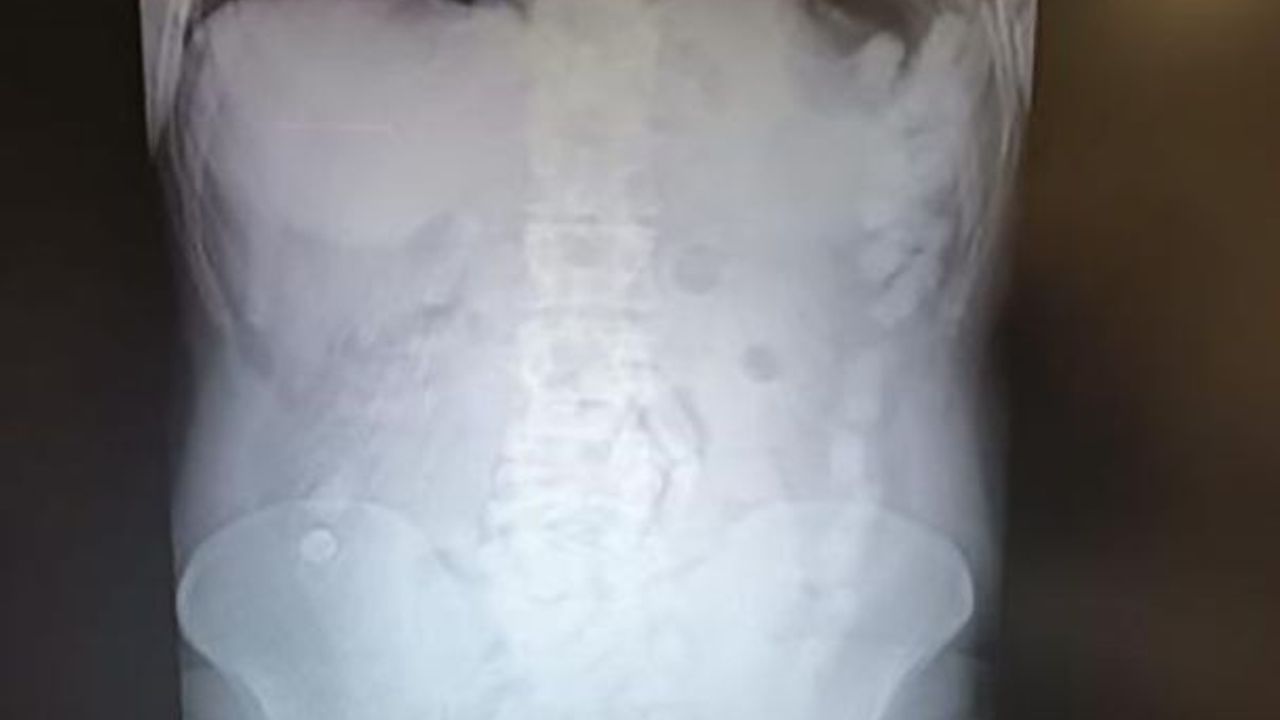

4 Mayıs 2024’te Kayseri İl Emniyet Müdürlüğü Narkotik Suçlarla Mücadele Şube Müdürlüğü ekipleri, yabancı uyruklu A.H.’nin ülkeye giriş yaparak üzerindeki uyuşturucu maddeleri Kayseri’ye getireceğini tespit etti. Şahsı takibe alan ekipler, yerini belirledikten sonra operasyon düzenledi. Kayseri Şehir Hastanesi’nde ultrason çekimi ile yapılan kontrolde şahsın midesinde çok sayıda kapsül olduğu belirlendi. Yapılan operasyonla şahsın midesinden çıkarılan 100 kapsülün içinde toplam 729 gram uyuşturucu madde ele geçirildi.